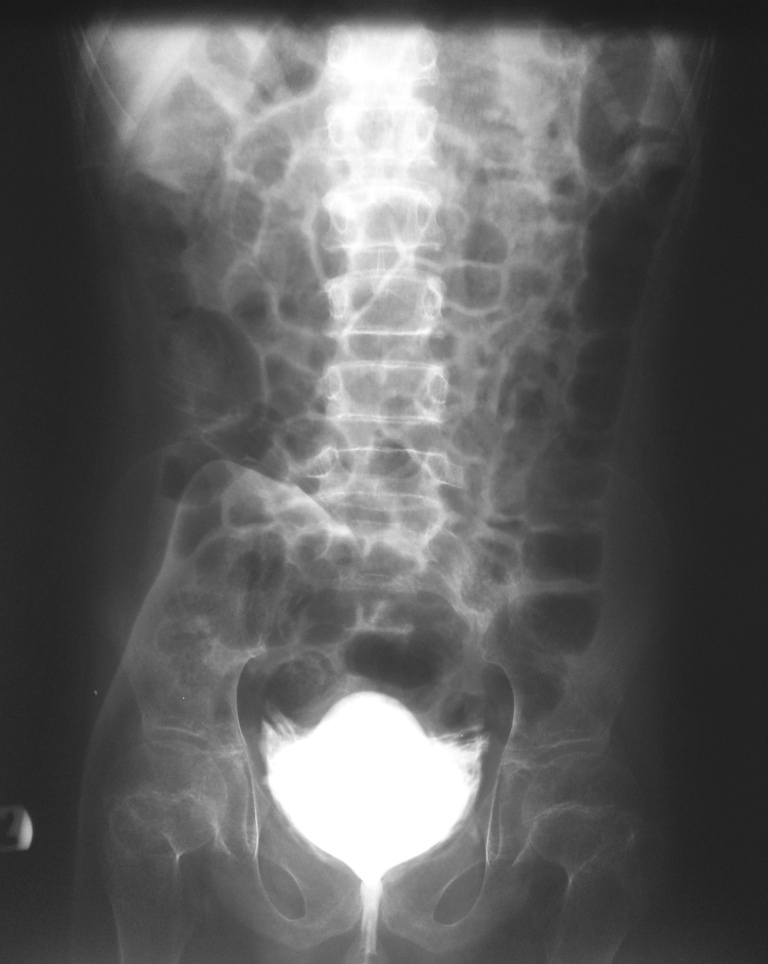

What is this procedure?

What percent of bladder ruptures are evident on post-void radiographs?

Cystogram

https://www.verywellhealth.com/cystogram-uses-side-effects-procedure-results-4173214